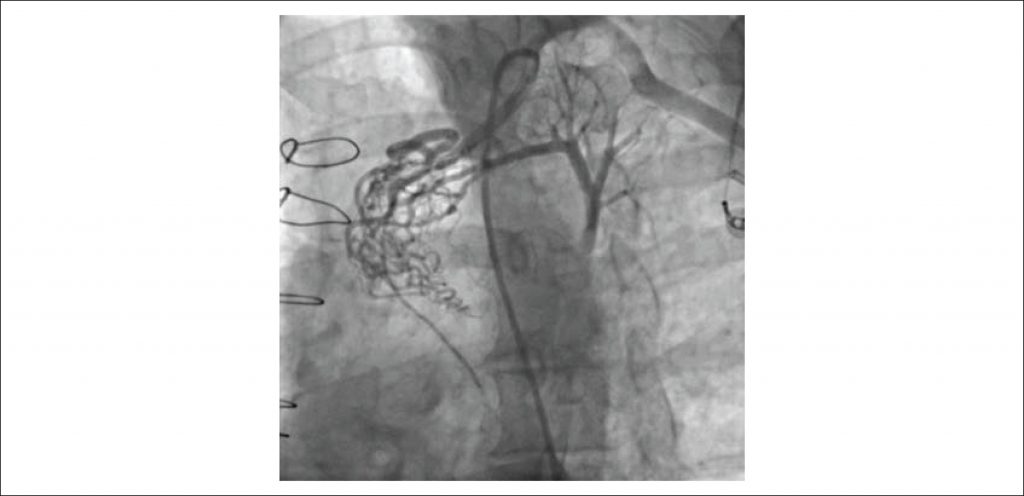

A 53-year-old man admitted to our outpatient clinic with symptoms of typical angina and shortness of breath despite optimal medical therapy. In his relevant history, he had a coronary artery bypass graft (CABG) operation in 2009 in which his LIMA was anastomosed to left anterior descending (LAD) and ramus artery sequentially. Coronary angiography including selective imaging of LIMA demonstrated a fistula formation originating from the proximal portion of the LIMA and draining to PA. After successful closure of fistula with transcatheter coil embolization, the patient was discharged without any complication and symptom.

In conclusion, although LIMA to PA fistula is an infrequent clinical condition, it should be considered as a potential cause of persistent angina after CABG operation. Treatment options include conservative medical therapy, surgical ligation and endovascular interventions. The best therapy should be individualised for each patient in respect to patient’s symptoms, surgical compatibility and anatomy of fistula.